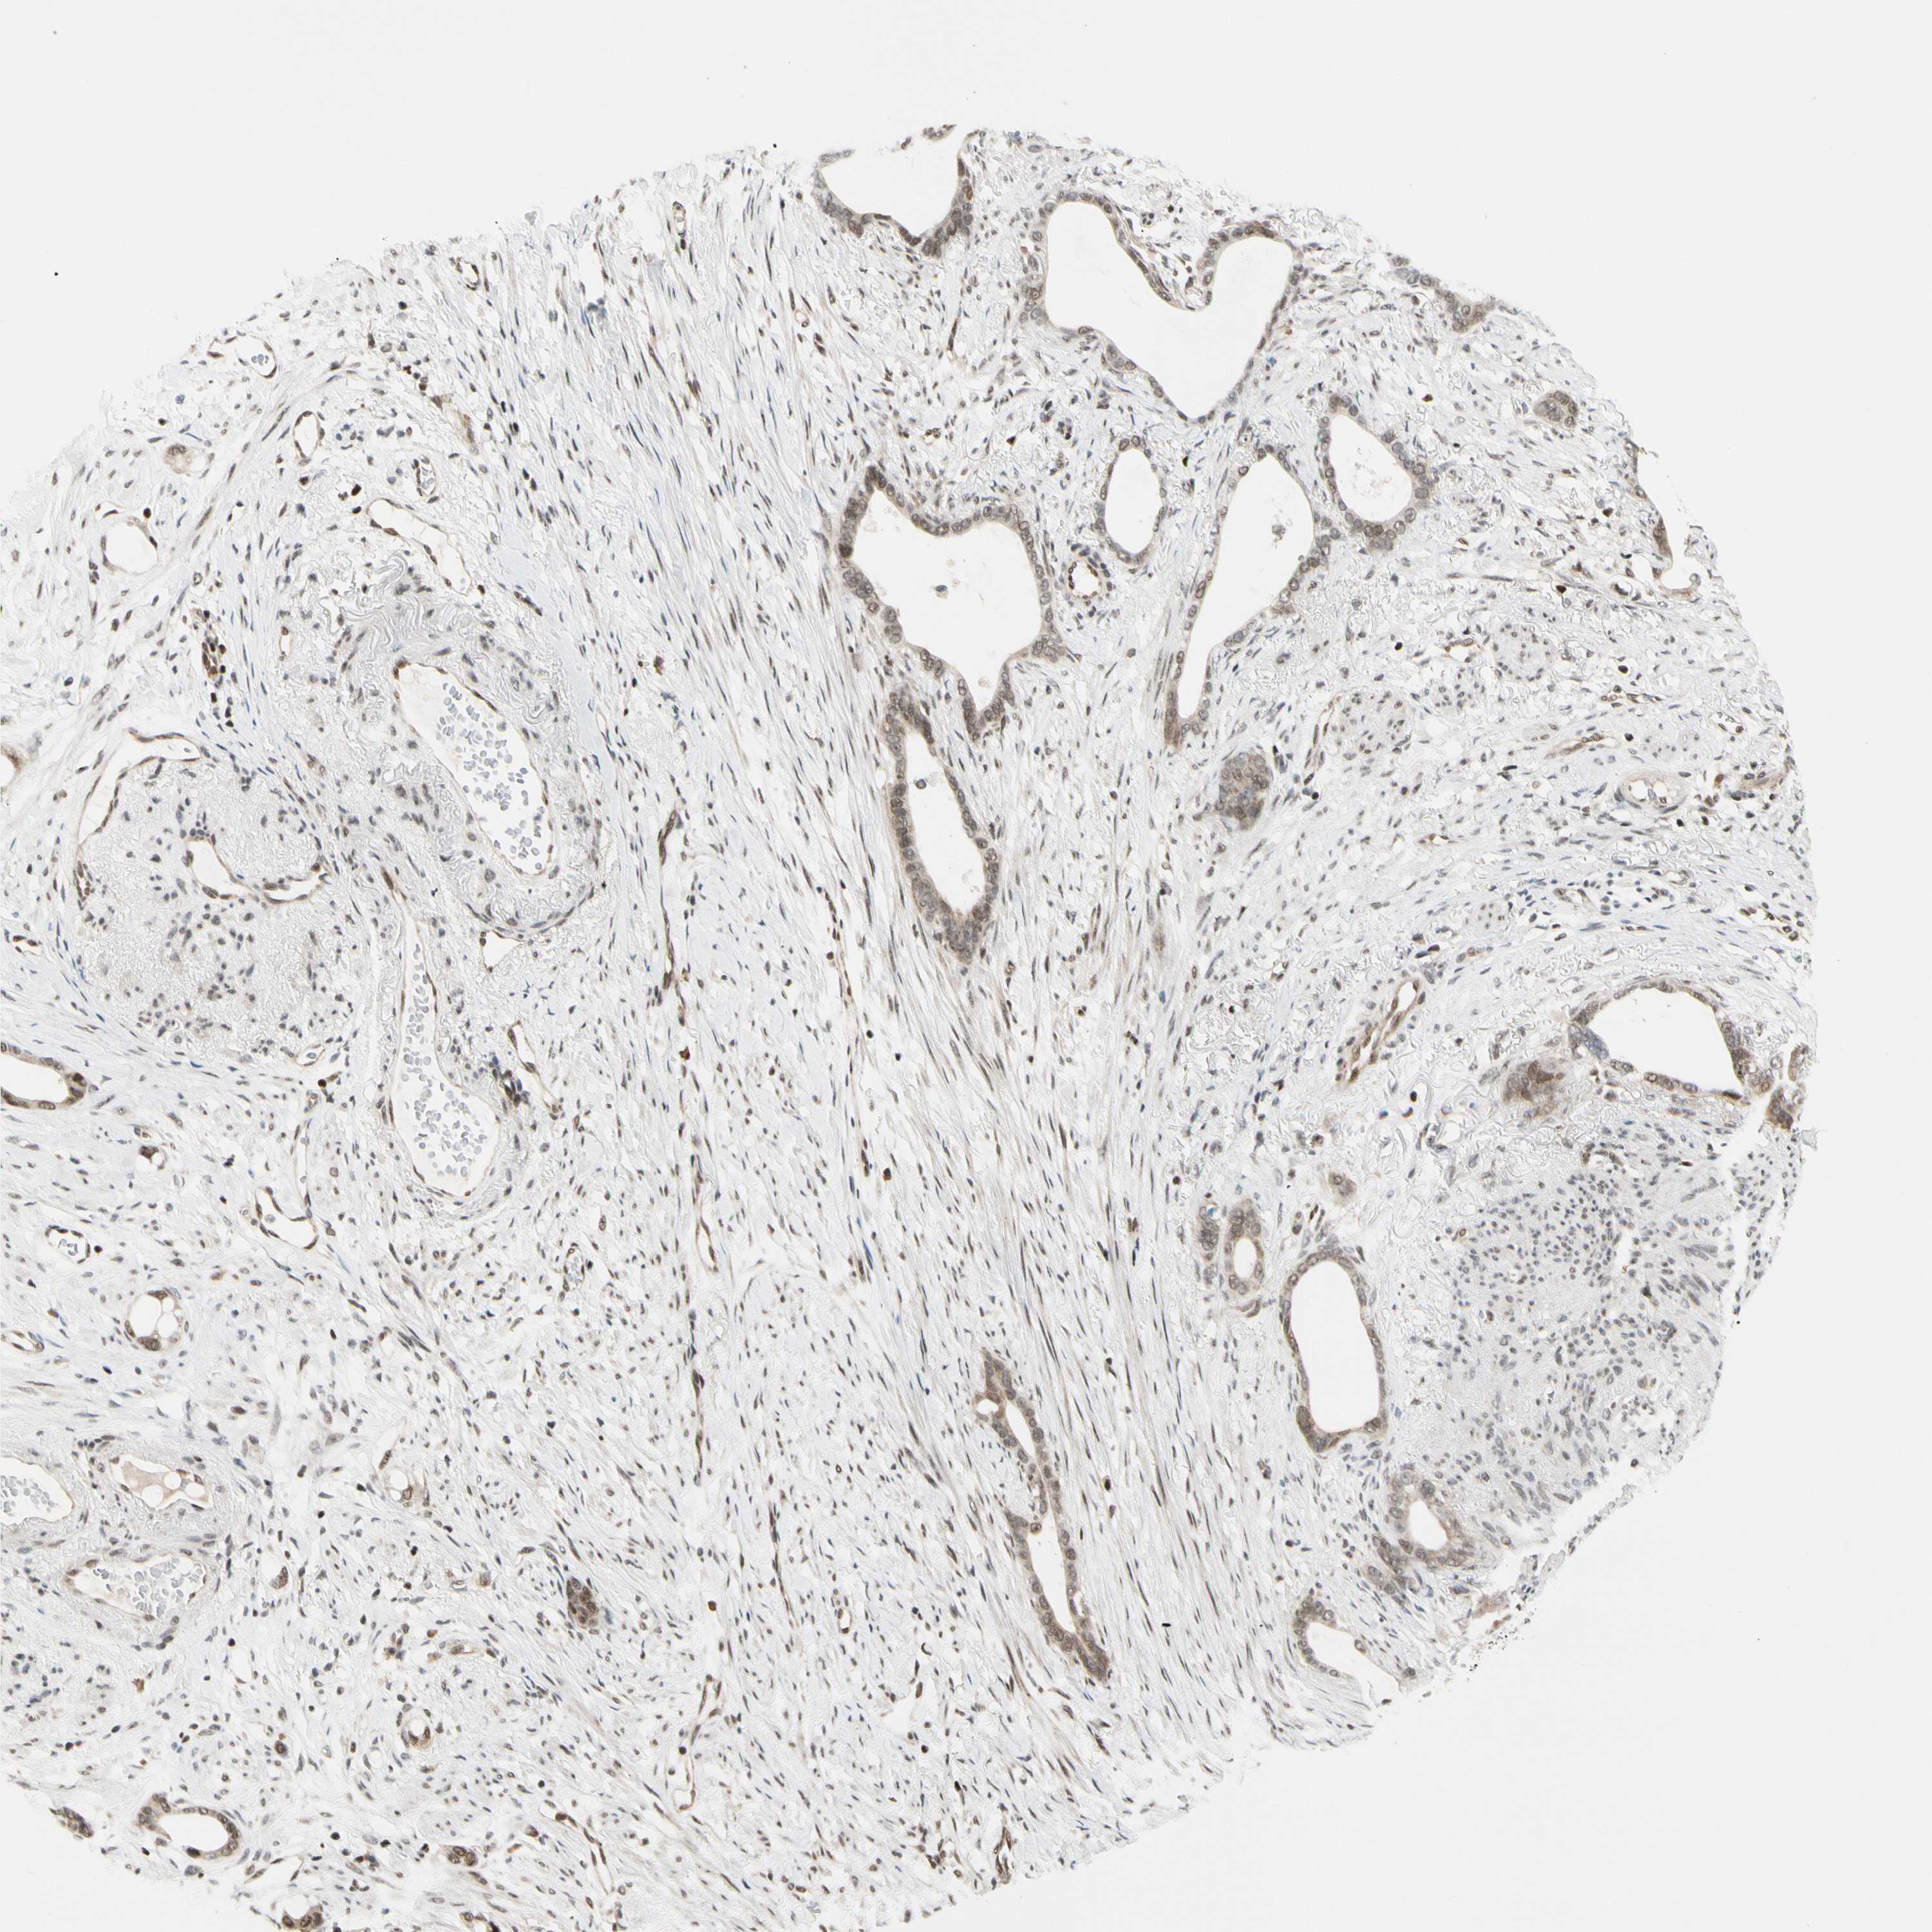

STOMACH CANCER - Protein expressioni

A mouse-over function shows sample information and annotation data. Click on an image to view it in a full screen mode. Samples can be filtered based on level of antibody staining by selecting one or several of the following categories: high, medium, low and not detected. The assay and annotation is described here.

Note that samples used for immunohistochemistry by the Human Protein Atlas do not correspond to samples in the TCGA dataset.

Antibody stainingi

Antibody staining in the annotated cell types in the current human tissue is reported as not detected, low, medium, or high, based on conventional immunohistochemistry profiling in selected tissues. This score is based on the combination of the staining intensity and fraction of stained cells.

Each image is clickable and will lead to virtual microscopy that enables deeper exploration of all samples and also displays staining intensity scores, fraction scores and subcellular localization as well as patient and tissue information for each sample.

Antibody HPA008736

Antibody CAB002224

Antibody CAB025546

Staining

High

Medium

Low

Not detected

Intensity

Strong

Moderate

Weak

Negative

Quantity

>75%

75%-25%

<25%

None

Location

Nuclear

Cytoplasmic/membranous

Cytoplasmic/membranous,nuclear

Adenocarcinoma, NOS

Adenocarcinoma, High grade